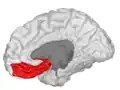

Orbitofrontal cortex

The orbitofrontal cortex (OFC) is a prefrontal cortex region in the frontal lobes of the brain which is involved in the cognitive process of decision-making. In non-human primates it consists of the association cortex areas Brodmann area 11, 12 and 13; in humans it consists of Brodmann area 10, 11 and 47.[1]

![]() Approximate location of the OFC shown on a sagittal MRI | |

Orbital gyrus shown in red.

Basal surface of cerebrum. Orbital gyrus shown in red.